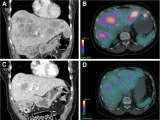

密苏里大学研究人员正在研发能够帮助肝癌患者的钇-90放射性同位素,为他们提供更多治疗选择并提升生存期。这项研究正在取得积极成果,有望为肝癌患者带来新的生存希望。